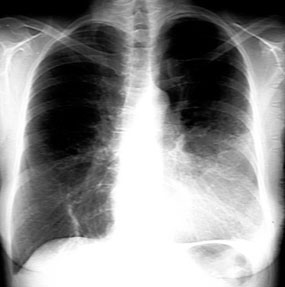

Lingular Consolidation

- Haziness in the left lower lung field

- Blunting of left costophrenic angle

- Loss of silhouette of left heart margin